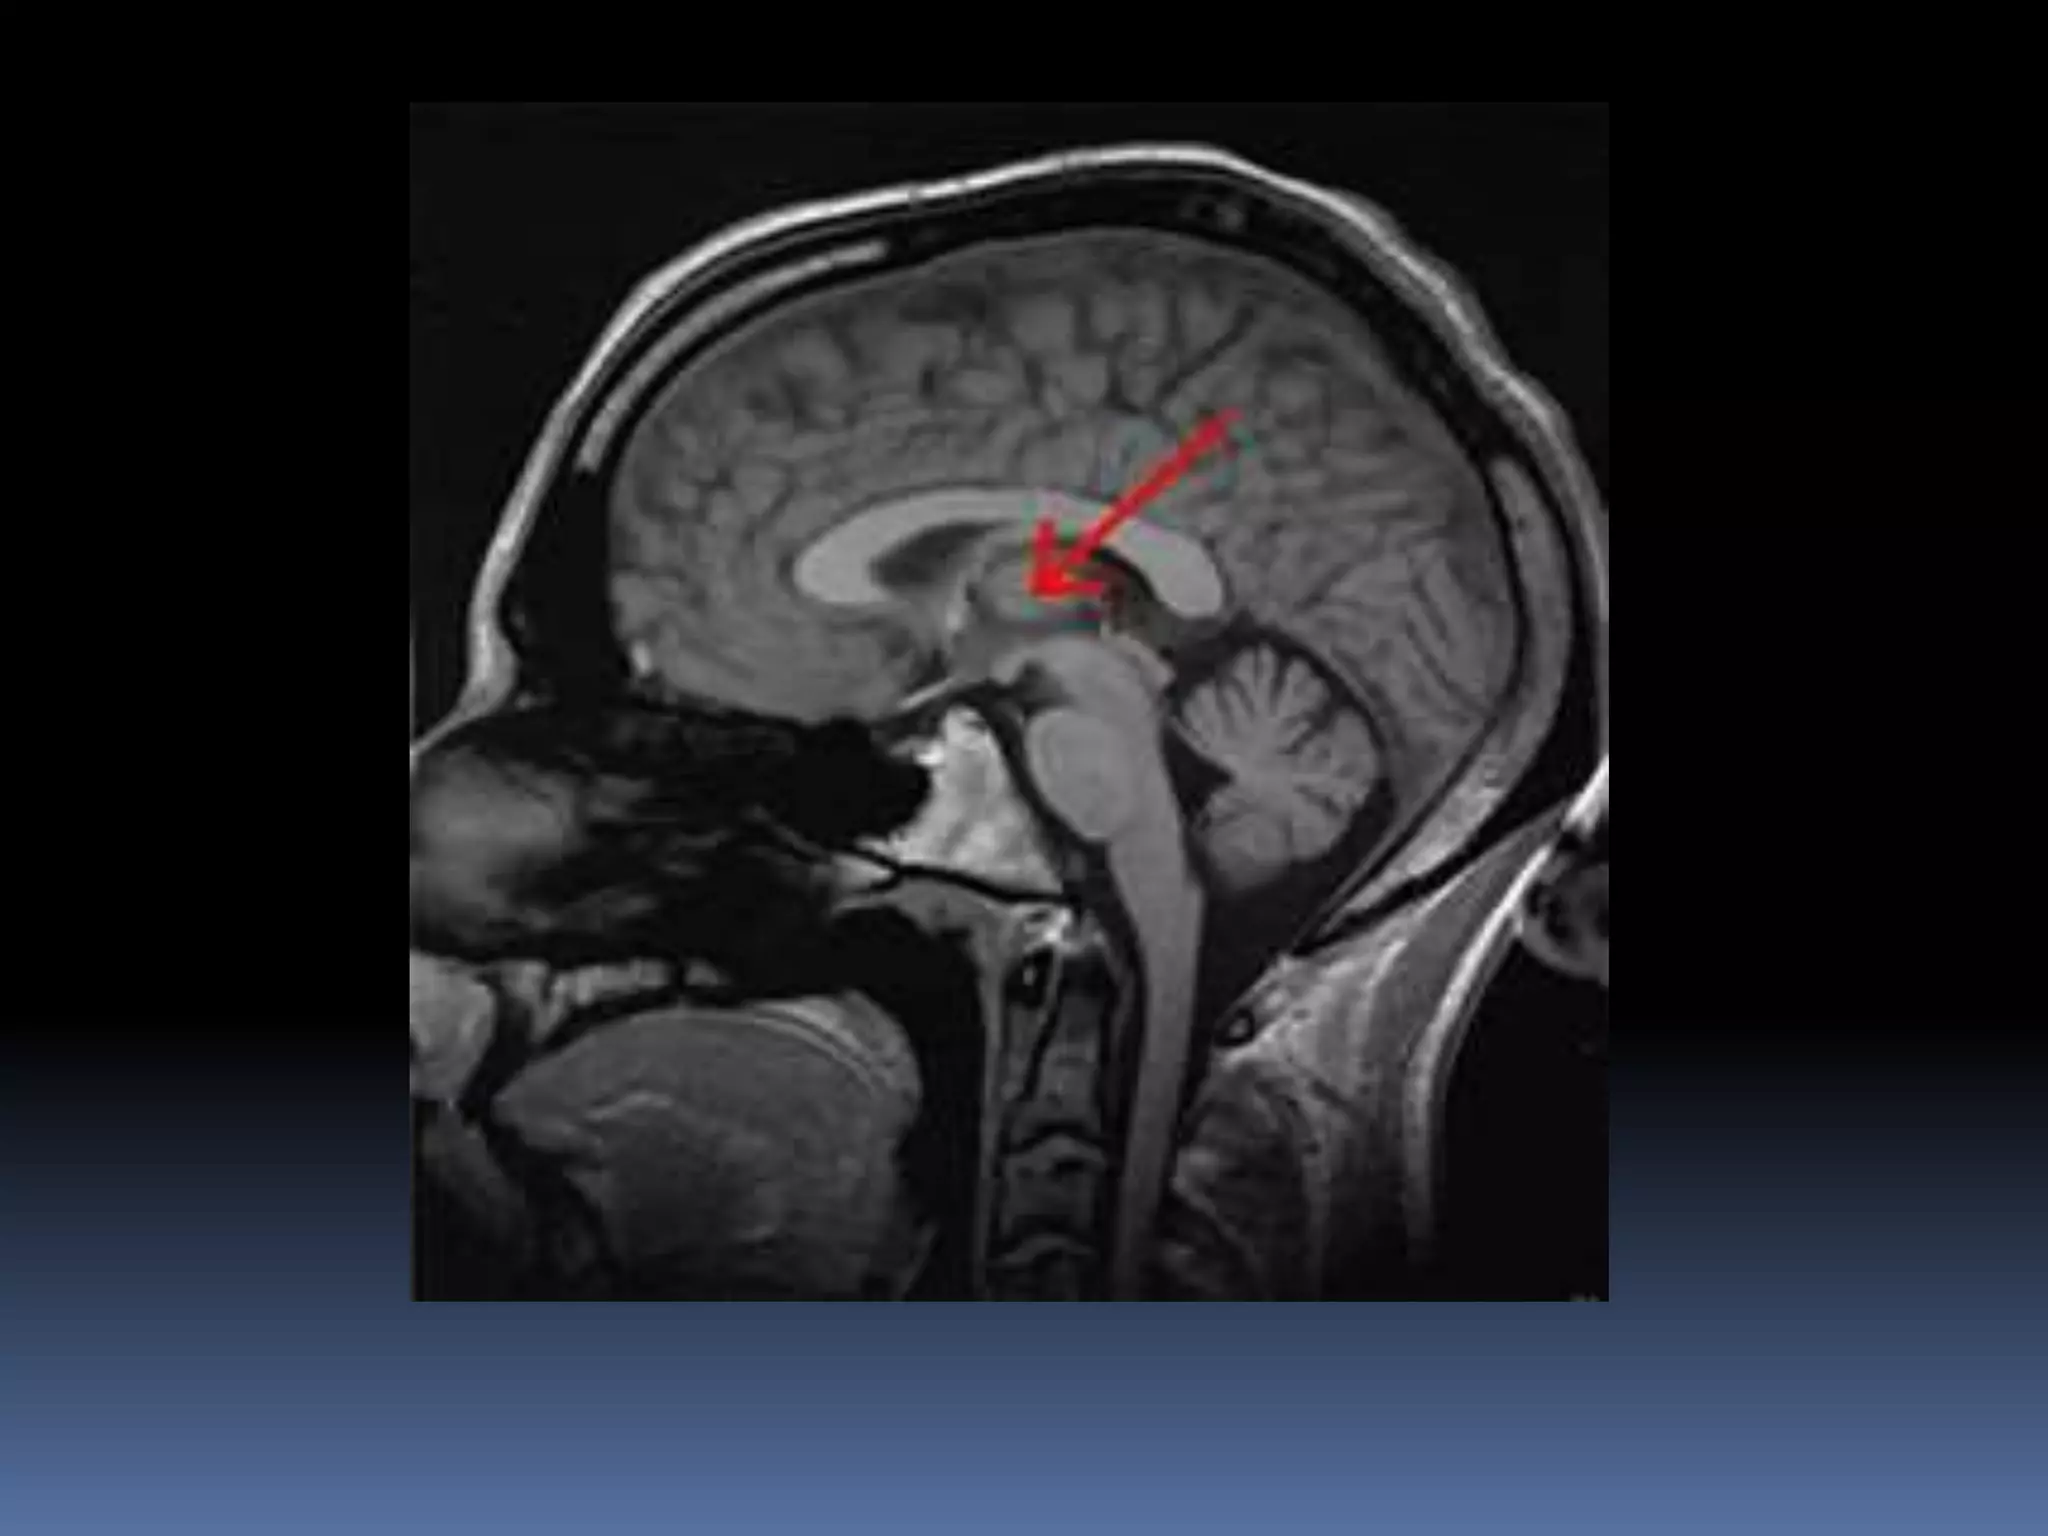

 Oval, nuclear mass

 Forms 80% 0f diencephalon

 Anterior extent- interventricular foramen

 Superiorly- transverse cerebral fissure, floor

of lateral ventricle

 Inferiorly- hypothalamic sulcus

 Posteriorly- overlaps midbrain